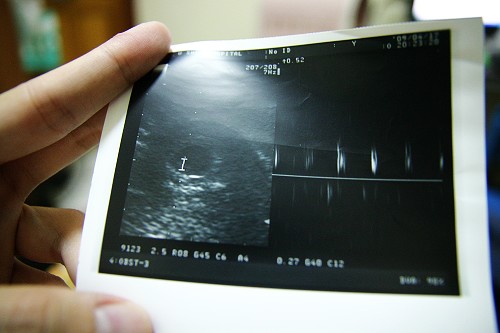

在4/17的時候去照了第二次的超音波

胚胎很明顯的比第一次大

也聽到了小傢伙的心跳

那種感動很難敘述